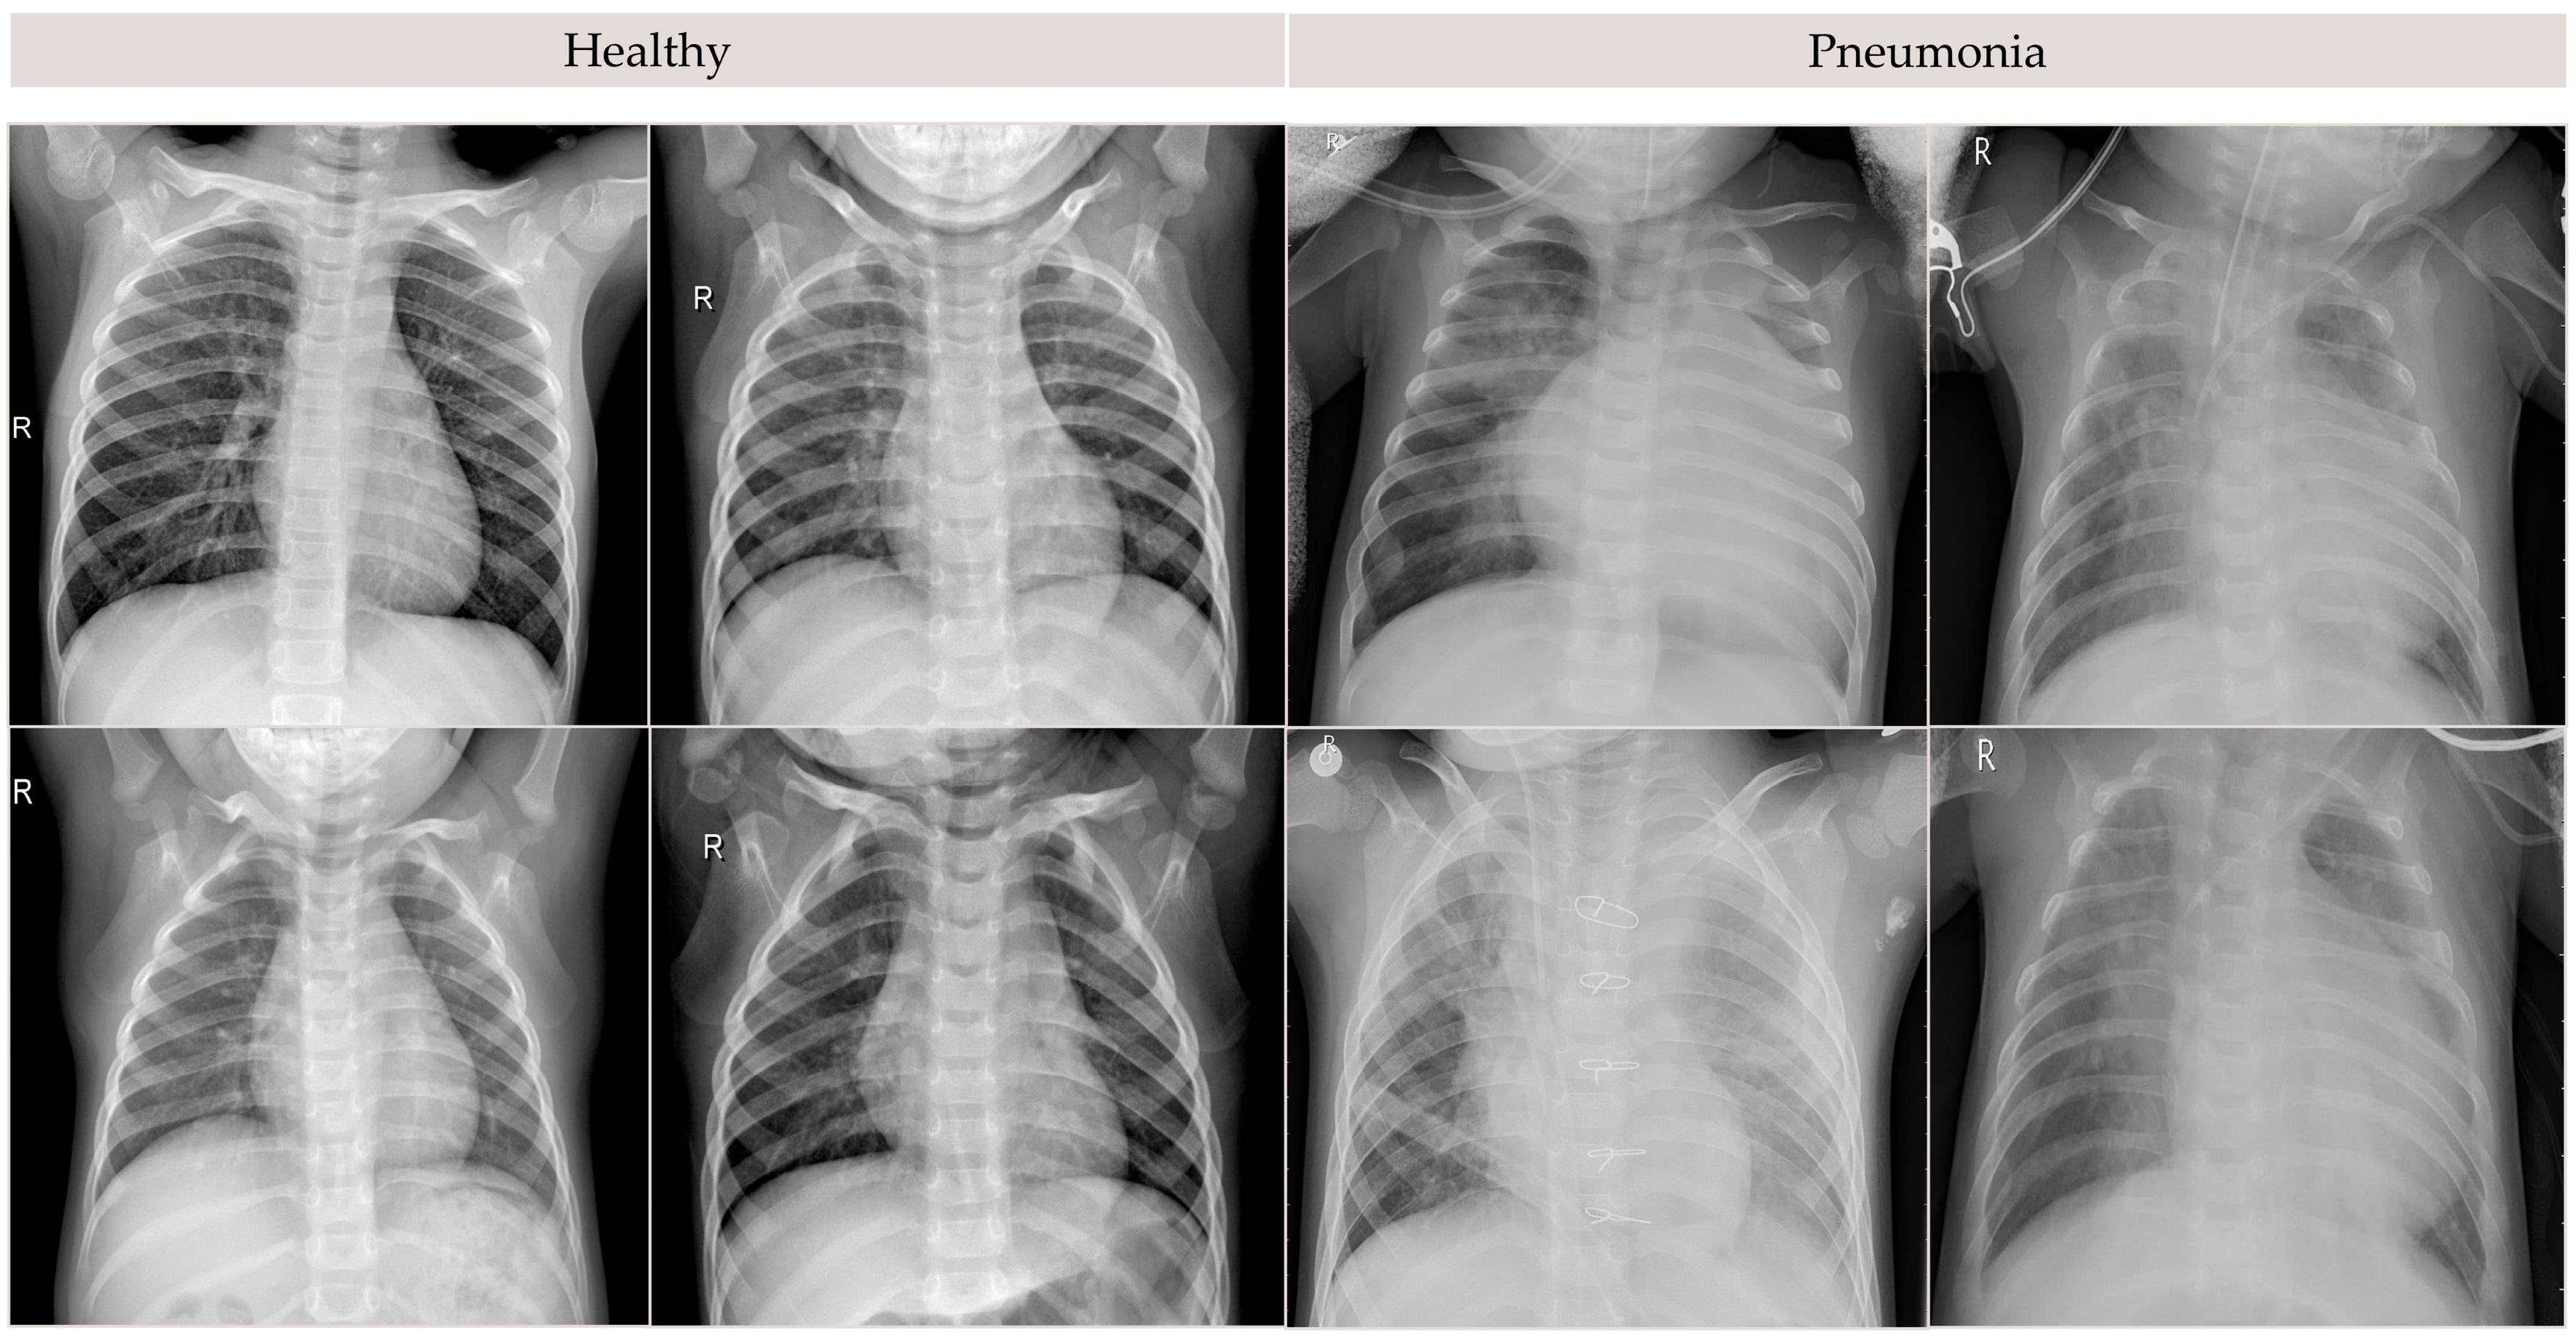

3.1. Data Preprocessing and Experimental Setup